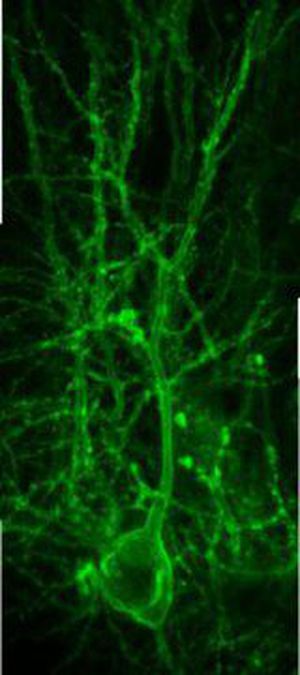

Understanding Neurological Diseases To demonstrate the technique's effectiveness, Zhu's team in Charlottesville and colleagues in China have used it to visualize a poorly understood neurotransmitter called acetylcholine. "Acetylcholine has an important role in how we behave because it affects our memory and mood," Zhu explained. "It affects Alzheimer's, schizophrenia, emotions, depression, all kind of emotion-related diseases and mental problems." (Acetylcholine also plays critical roles elsewhere in the body, such as regulating insulin secretion in the pancreas and in controlling stress and blood pressure.) Drugs designed to combat Alzheimer's disease actually inhibit acetylcholinesterase, an enzyme that degrades acetylcholine, to boost the effect of diminishing acetylcholine released in the brain, Zhu said. But doctors haven't fully understood how the drugs work, and there's been no way to determine just how much inhibition is needed. "These drugs are not very effective," he said. "They only offer a minor improvement, and once you stop the drug [the symptoms] just seem much worse. So probably in trying to treat these patients, you temporarily enhance them but you actually make them even worse."